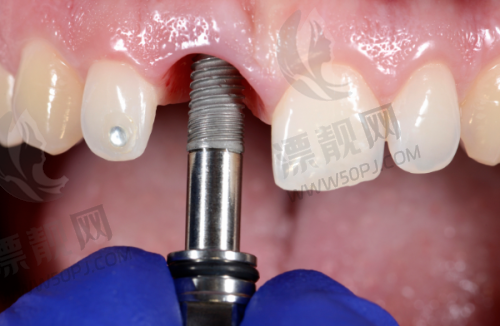

技术亮点:支持即刻种植、微创种植,全口、半口种植也能轻松搞定。医生团队中有王锋、刘诗奇、孙玉枫等骨干成员,各有所长。

技术亮点:主打数字化种植,采用CBCT、种植导板,有效提升正确率。

优势:主打数字化诊疗,设备齐全,支持远程会诊及3D导板种植。